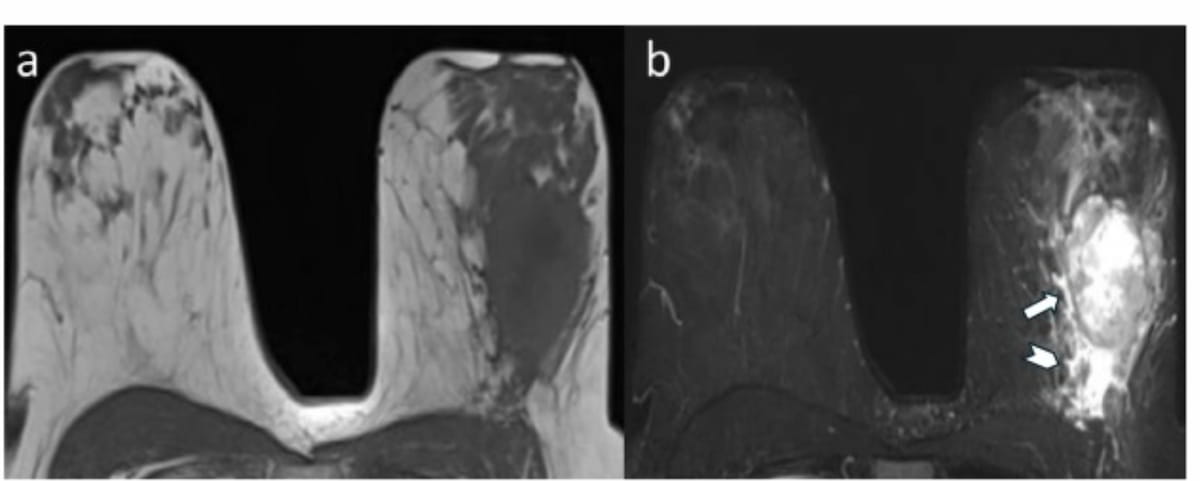

In a seven study meta-analysis with a total of 493 cases involving high-risk breast lesions, researchers found that contrast-enhanced breast MRI did not miss any cases of invasive breast cancer.

For patients with triple-negative breast cancer being treated with neoadjuvant chemotherapy and immunotherapy, MRI demonstrated a 94.3 percent sensitivity for predicting pathologic complete response, according to a new study.